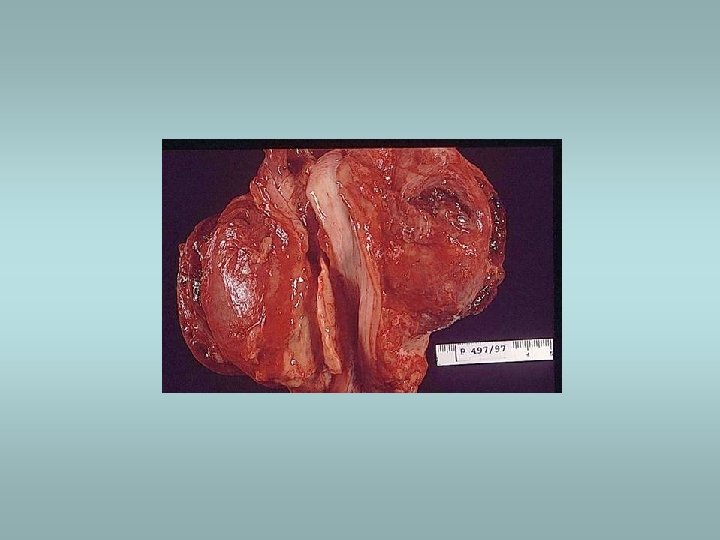

Adrenal medulla Phaeochromocytoma ü Catecholamine production – hypertension ü 85% in medulla (extra-adrenal tumors designated paragangliomas) ü Sporadic (90%) or associated with familial syndromes (MEN, von Hippel-Lindau, von Recklinghausen) ü Histologically – pleomorphism, mitotic activity - however there are no reliable histological predictors of malignancy!! ü Only criterion of malignancy – metastasis Other tumors – neuroblastoma, ganglioneuroma